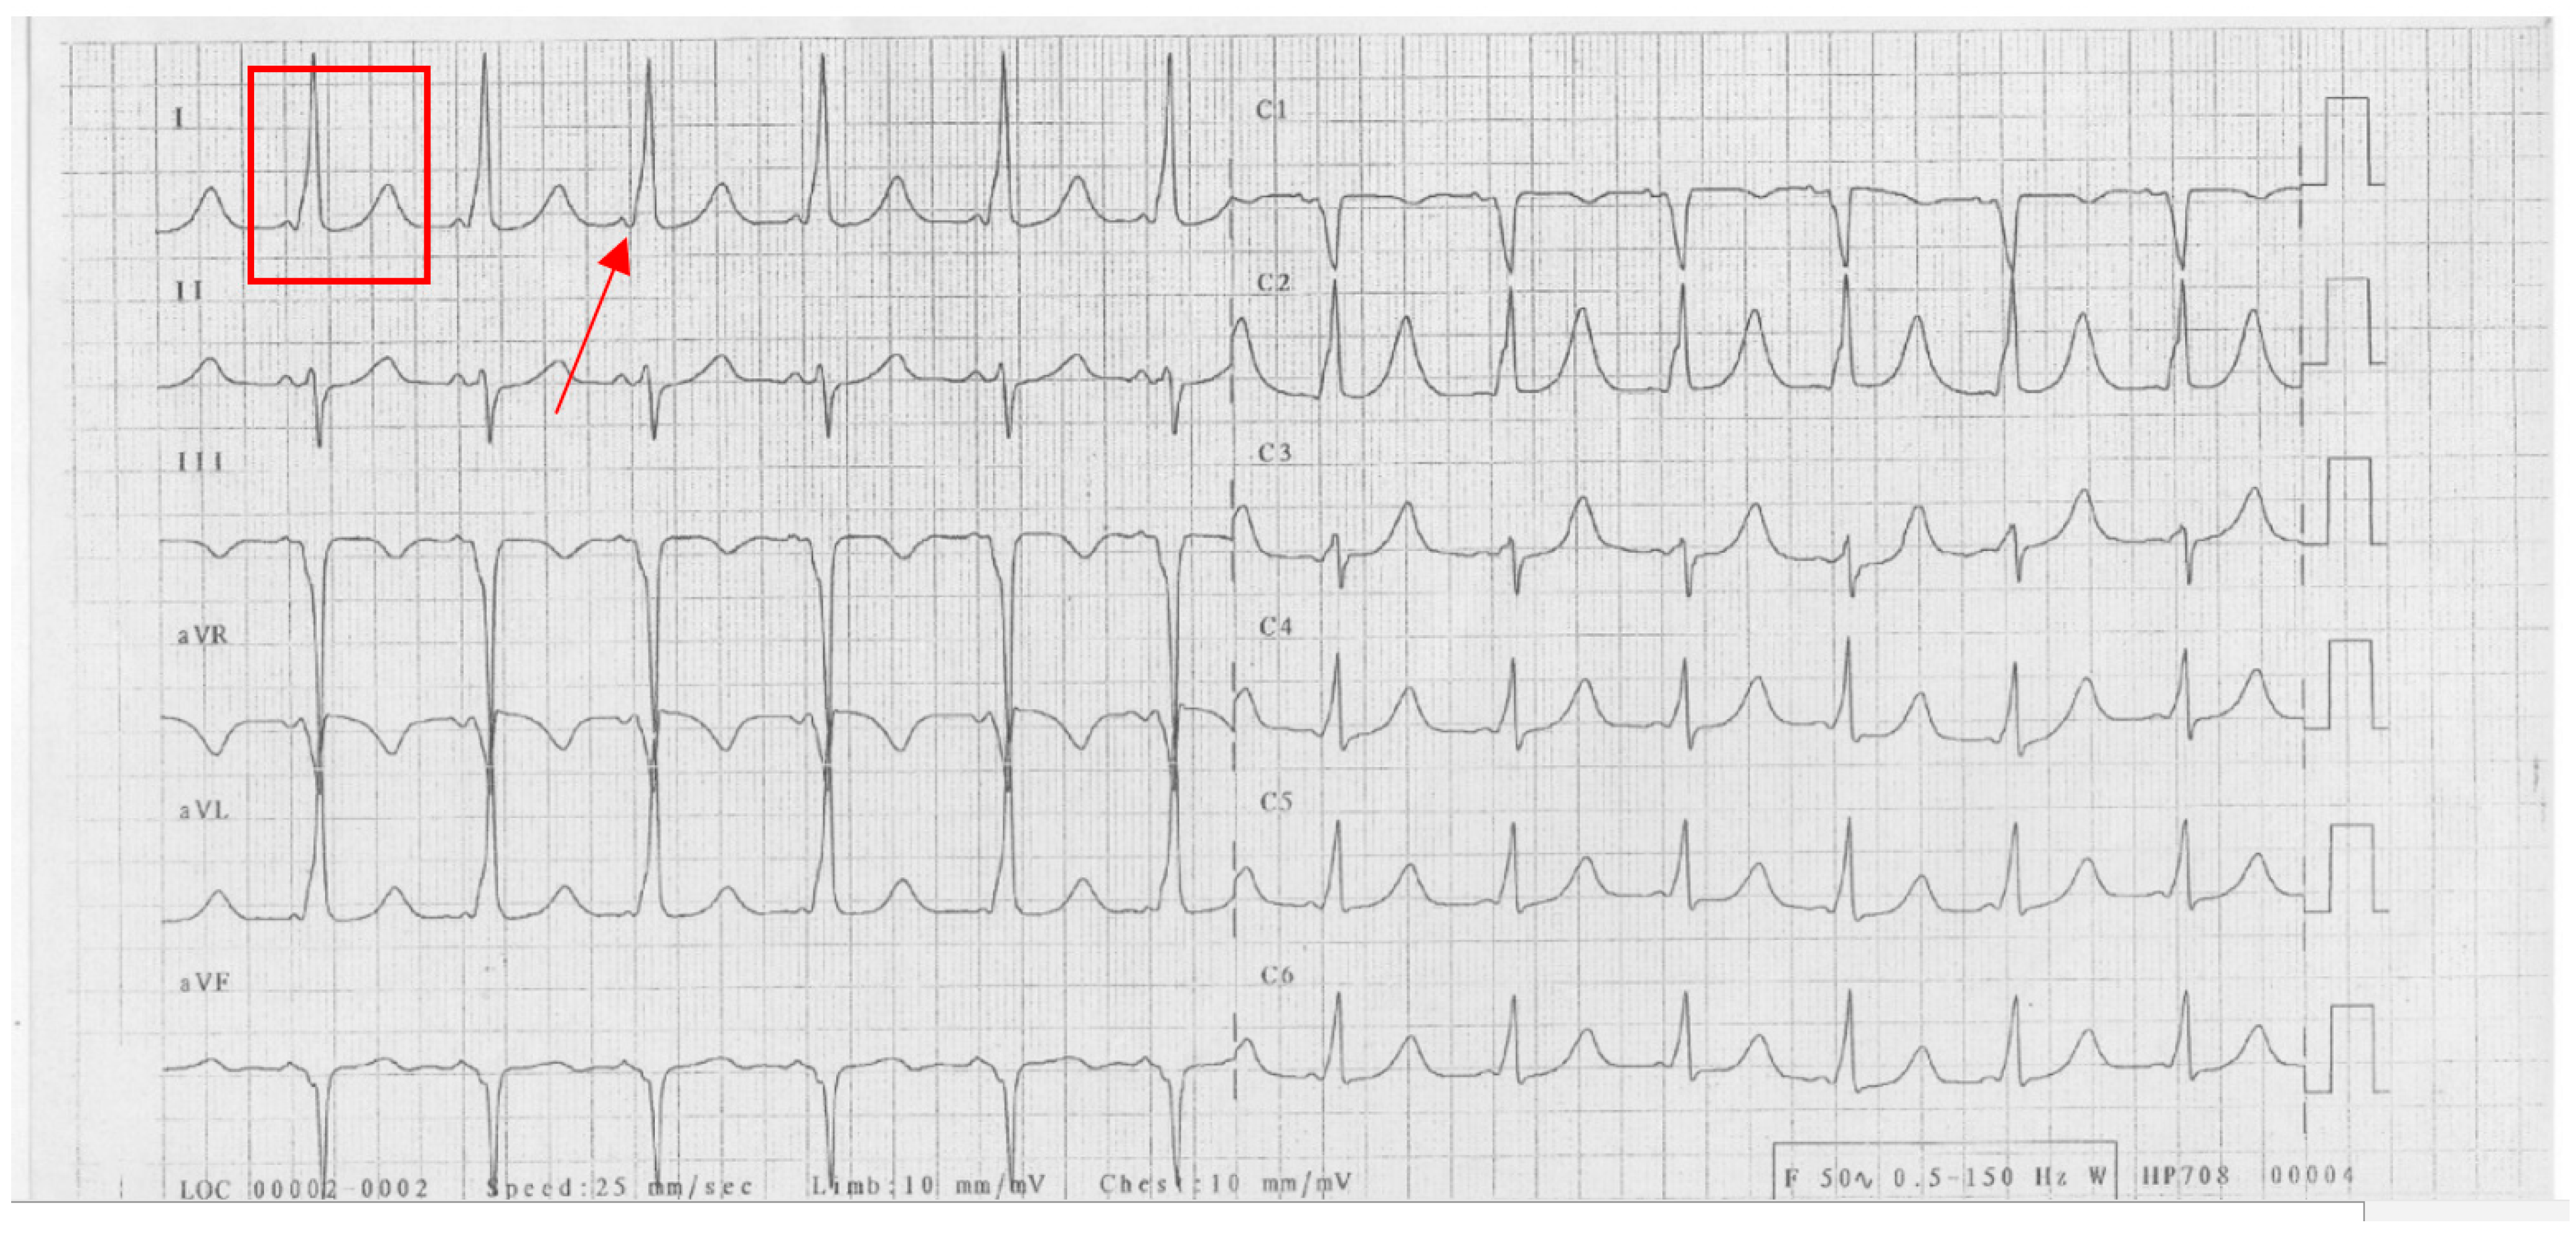

A 26-year-old woman presented with recurrent syncope. Clinical examination and echocardiography showed no signs of structural heart disease. The ECG in sinus rhythm showed a short PR interval, wide QRS (150 ms) due to a delta wave, and a QT interval increase (QT 580 ms, QTc 648 ms) (Figure 1).

Figure 1.

Patient’s baseline ECG. Red rectangle denotes the long QT interval; the arrow indicates the delta wave.